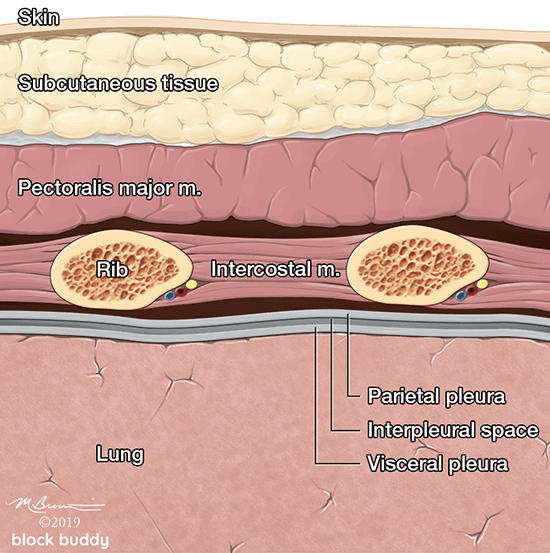

Anatomy

- The ribs will appear as convex hyperechoic lines with acoustic shadows.

- Located between the ribs are the hypoechoic intercostal muscles and the smooth, thin hyperechoic pleural line.

- These structures form the “bat sign”: the shadow of the ribs form the wings, while the area between the ribs represents the body.

Lung Sliding

- The pleural line is comprised of the parietal and visceral pleura, but will appear as a single, thin hyperechoic line.